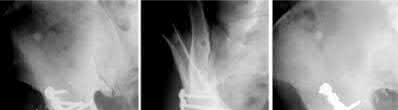

Figures A and B are pre-operative and intra-operative radiographs of a 67-year-old male that has undergone a left total hip arthroplasty under general anesthesia. The patient had no motor deficits preoperatively. During the operation, the trial acetabular and femoral components were positioned and reduced with no complication. Intraoperative leg lengths were equal. Before implanting the real components, the surgeon and anaesthesiologist performed a wake up test, which revealed that the patient was unable to dorsiflex the left foot. What would be the most appropriate next step in the management of this patient?

1) Urgent electromyogram and nerve conduction study

2) Continue with sized trial components and observe the motor function in surgical recovery area

3) Remove all implants and insertion of cement spacer

4) Perform a shortening subtrochanteric osteotomy

5) Urgent neurology consult

This patient has undergone a left THA with significant leg lengthening. The biggest concern is stretch to the sciatic nerve. The most appropriate step at this stage would be to perform a subtrochanteric osteotomy to decrease leg length and sciatic nerve stretch.

Patients with DDH that have undergone a large limb-lengthening procedure are at a greater risk due to the significant stretch of the sciatic nerve. Intraoperative procedures that have been shown to prevent this outcome include good pre-operative planning, limb lengthening